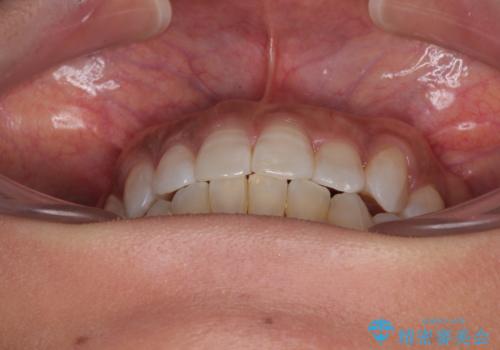

咬合力による臼歯離開は顎間ゴムで改善されましたが、それとは別に下顎小臼歯がマウスピースに追従せず、補正のためのゴムかけが必要となりました。

大変なゴムかけ作業を頑張っていただき、無事に治療を終えることができました。